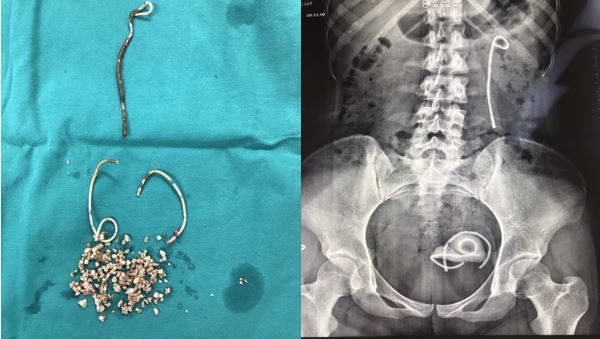

Khoảng hơn 1 năm nay bệnh nhân có biểu hiện thường xuyên đái rắt, đái buốt nên chị đã tới Khoa Ngoại Tiết niệu - Bệnh viên Trung ương Quân đội 108 khám và kiểm tra, bác sĩ phát hiện có 1 stent JJ bị gãy thành 3 đoạn, 1 đoạn trên thận, 2 đoạn trong bàng quang.

Stent jj bị bỏ quên trong niệu quản bệnh nhân suôt 5 năm.

Stent jj trong niệu quản nữ bệnh nhân này đã được đặt từ 5 năm trước tuy nhiên loại stent này thường không được lưu giữ quá 3 tháng trong cơ thể. Các bác sĩ Viện 108 còn phát hiện xung quanh chiếc stent bị bỏ quên có rất nhiều sỏi bám làm bệnh nhân đau buốt và mất máu, đặc biệt bệnh nhân còn bị sỏi bàng quang với kích thước lớn hơn 3 cm.

Tại khoa Ngoại Tiết niệu, các bác sỹ đã tiến hành phẫu thuật bằng phương pháp nội soi lấy sỏi qua da và tán sỏi bàng quang cho nữ bệnh nhân T. Sau phẫu thuật một tuần bệnh nhân đã ổn định và được ra viện.